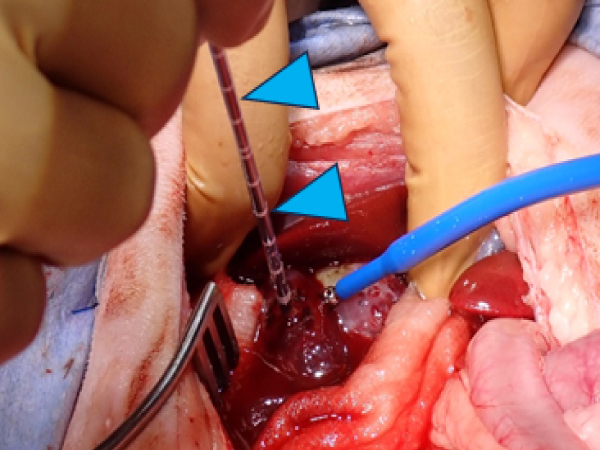

肝臓腫瘍のセカンドオピニオンで来院され、CTを撮影したところ肝臓の根元に腫瘍が認められました。 太い血管にかなり密接しており完全に摘出できるかわかりませんでしたが摘出を目的に開腹手術を行ないました。 手術時にやはり内側右葉という肝臓の根元に腫瘍が存在していました。まずは腫瘍に入ってきている血管を結紮していきます。 順番に結紮していったところやはり最後に太い血管と張り付いており完全に剥離するのが困難でした。 そこでアブレーションを組み合わせることで腫瘍を縮小していくこととしました。 周囲の組織に影響が出ないよう周囲を生理食塩水で冷やしながら実施しました。

開腹直後の肝臓腫瘍(黄色矢頭)

流入する栄養(肝動脈、門脈)血管を止めたあとの肝臓腫瘍血流がなくなり色が悪くなっている

肉眼にて器具のアンテナ(青矢頭)挿入位置を決定してアブレーションを実施している